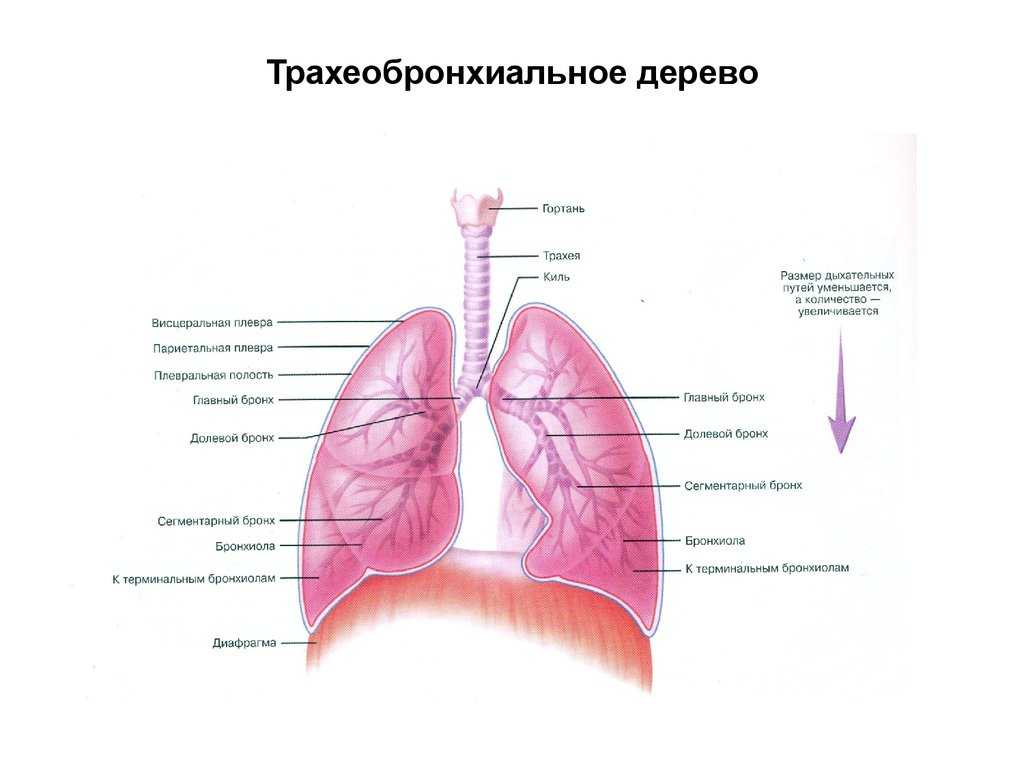

В трахеобронхиальном дереве в организме человека вырабатывается небольшое количество слизи, предусмотренное природой для удаления из органов дыхания микробов и чужеродных примесей (пыли, мелких частиц и соединений, неизменно присутствующих в воздухе).

Будучи естественным антибактерицидным средством, прозрачная слизь у детей и у взрослых, в небольшом количестве не раздражает рецепторы и не провоцирует защитный кашлевой рефлекс.